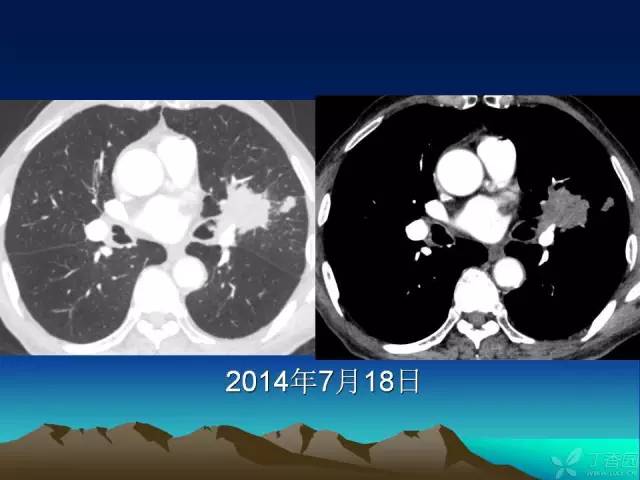

【PPT】早期肺癌易漏诊征象分析